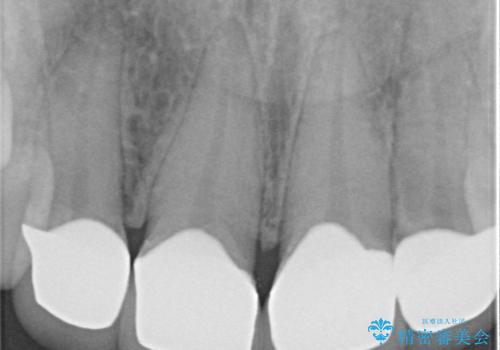

- 大きすぎる上顎前歯と、隙間の空いた下顎歯列を気にして来院された患者様です。

上顎前歯にはセラミッククラウンが装着されており、顔や他の歯と比較して幅の大きい状態でした。

下顎前歯は空隙歯列弓であったので、アンカースクリューとワイヤー装置を用いてスペースを閉じていくこととし、上顎前歯は矯正治療用の仮歯に置き換えた上で、仮歯の大きさを削って小さくしながら、上下前歯部の部分矯正を行うこととしました。